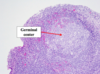

Gross pathologic features of Wilms tumor?

Nodular

Gray to tan-white

Soft, friable, fleshy

Wilms Tumor

What is the significance of this in WIlms Tumor?

ANAPLASIA

Determines the Prognosis of Wilms tumor

- Pleomorphism, hyperchromatism, abnormal mitoses –> more aggresssive; higher resistance to chemotherapy

- Stage matters also w/ Prognosis*